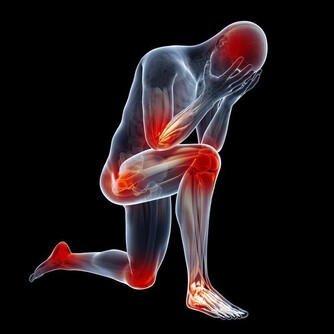

中醫認為,肺與秋季相應,而秋季乾燥,氣燥傷肺,肺氣虛則機體對不良刺激的耐受性下降,易產生疾病,因為需要潤燥、養陰、潤肺。